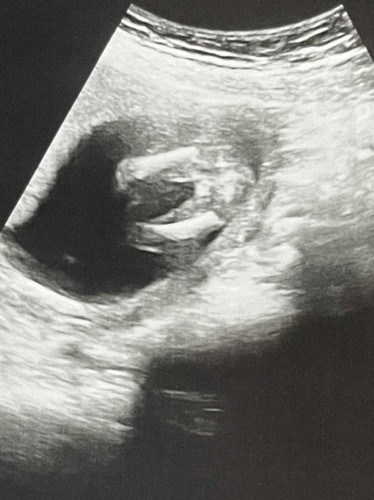

อันตร้าซาวน์ตอน15w3dคุณหมอบอกผู้หญิง80%

ตอนนี้17w2d เรากลัวซื้อของเตรียมแล้วจู๋น้องโผล่ทีหลังจัง

เอากลางๆ ไปก่อนคะแม่ ตอนแรกบ้านนี้ซาวตอน13 วีค บอกผู้หญิง80% พอมา16 บอกผู้ชาย แต่ก็ไม่พีคเท่าที่พี่เข้าไปตรวจก่อน บอกชายมา 7 เดือน ไป2หมอก็ชาย พอ8เดือนบอกหญิง คุยยังไม่ทันขาดคำเรยคะแม่ หมอเรียกคิวเข้าไป ของตัวเองก็เป็น🤣 แต่แม่ก็คิดว่าชาย ไม่เปลี่ยนแล้วละคะ แค่ยังไม่เห็นไข่😁